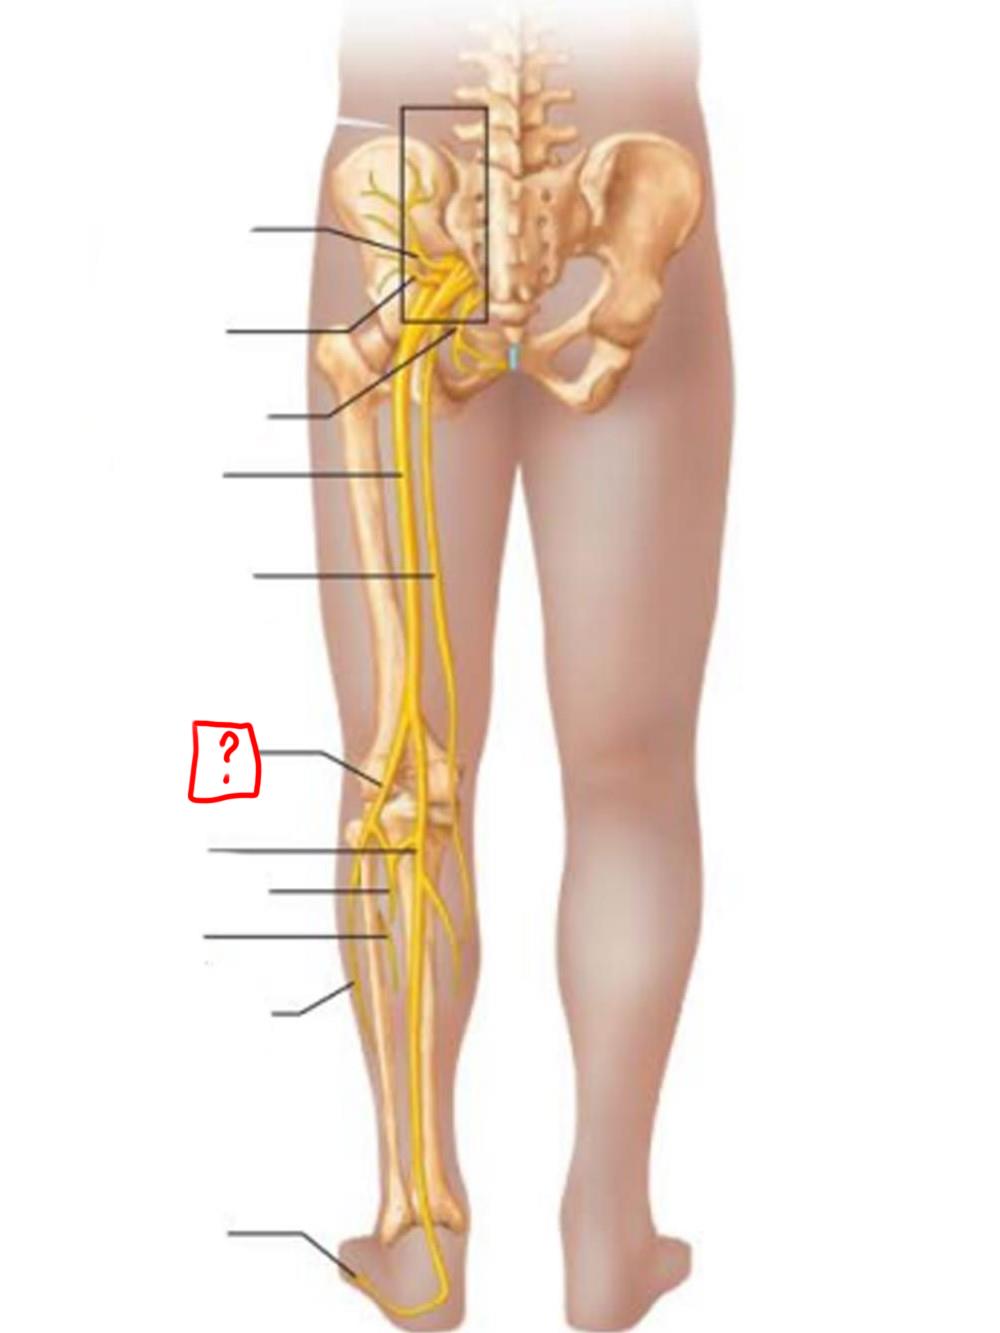

sciatic

posterior femoral cutaneous

common fibular

tibial nerve

sural (cut)

deep fibular

superficial fibular

plantar branches